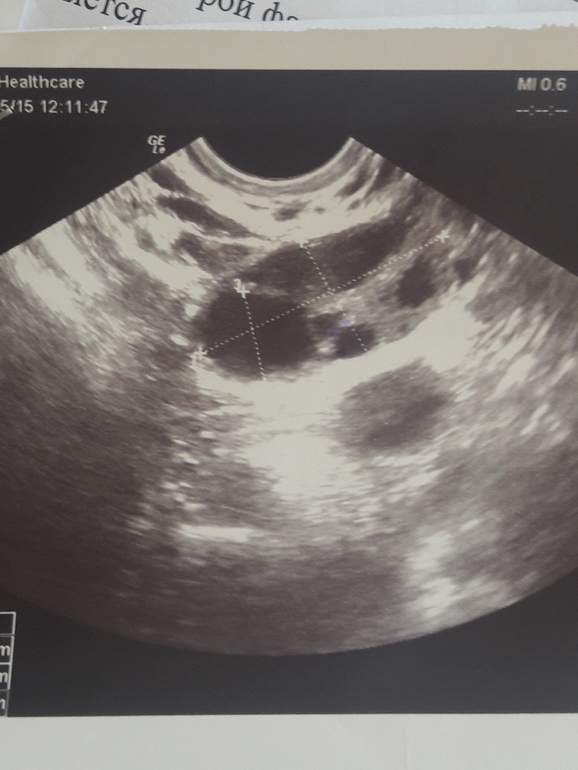

вот-подтвержденное ЖТ.(правда оно беременное,пара дней задержки).Светящиеся области вокруг-кровоток..

Во всех этих узи где есть подтвержденное ЖТ у меня написано жидкости в позадиматочном не обнаружено